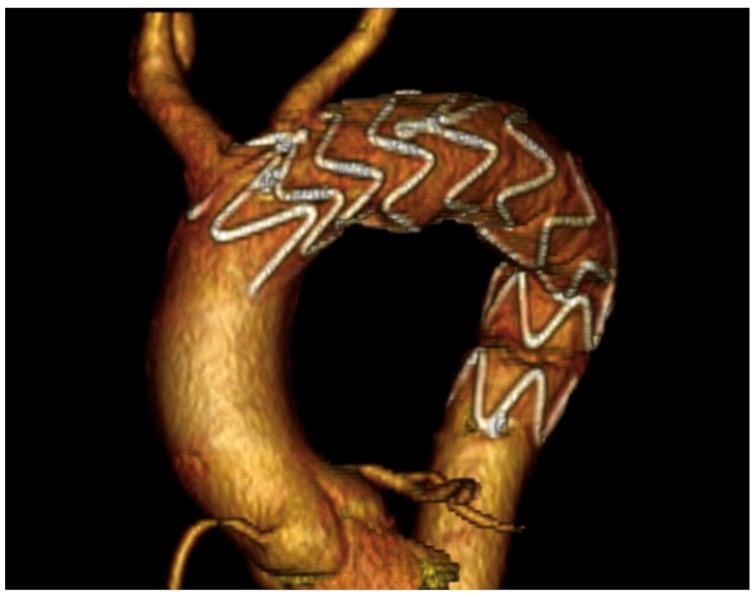

Grade I-II blunt traumatic aortic injuries (BTAIs) are typically managed conservatively, but their long-term progression is poorly understood. Chronic pseudoaneurysms may develop years after the injury, often remaining asymptomatic and being incidentally diagnosed. Two cases of post-traumatic aortic pseudoaneurysms, detected 20 and 25 years following conservatively managed BTAIs, are reported. Additionally, a comprehensive review of all post-traumatic pseudoaneurysms reported in the MedLine (PubMed.gov, U.S. National Library of Medicine, National Institute of Health) database between January 1984 and December 2024 was performed. Both our patients underwent successful hybrid procedures, with no complications at the 1- and 4-year follow-ups. Our literature review identified 37 patients across 22 studies, with 32.4% presenting asymptomatically or incidentally diagnosed through routine imaging, between 1 month and 50 years after the initial trauma. In 37.8% of cases, the patients underwent open or endovascular repair. This case series and literature review emphasize the importance of long-term follow-up for patients with conservatively managed BTAIs, as chronic complications such as aortic pseudoaneurysms can arise decades later. Continuous surveillance is critical to ensure early detection and management.

I-II级钝性创伤性主动脉损伤(BTAIs)通常采用保守治疗,但其长期进展情况尚不清楚。慢性假性动脉瘤可能在损伤数年之后形成,常常没有症状,而是在偶然检查时被诊断出来。本文报告了两例在保守治疗BTAIs后20年和25年发现的创伤后主动脉假性动脉瘤病例。此外,还对1984年1月至2024年12月期间MedLine(美国国立医学图书馆、美国国立卫生研究院的PubMed.gov)数据库中报告的所有创伤后假性动脉瘤进行了全面综述。我们的两名患者均成功接受了杂交手术,在1年和4年随访时均无并发症。我们的文献综述在22项研究中确定了37例患者,其中32.4%在初次创伤后1个月至50年之间没有症状或通过常规影像学检查偶然被诊断出来。在37.8%的病例中,患者接受了开放手术或血管腔内修复。这个病例系列和文献综述强调了对接受保守治疗的BTAIs患者进行长期随访的重要性,因为诸如主动脉假性动脉瘤等慢性并发症可能在数十年后出现。持续监测对于确保早期发现和治疗至关重要。